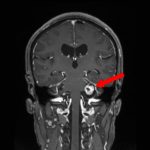

707

'25年12月

80代

髄膜腫

頭蓋内腫瘍摘出術

No.’25_109 手術前1

No.’25_109 手術前2

No.’25_109 摘出 前

No.’25_109  摘出 中

No.’25_109 摘出 後